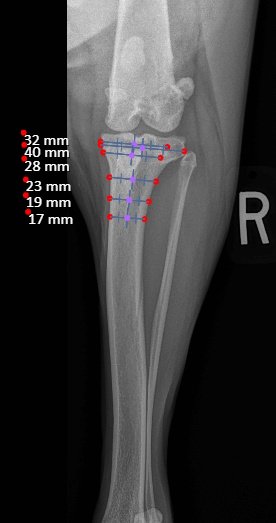

Post Surgical Radiographs

While the patient is still anesthetized, the patient is taken into radiology for post-surgery radiographs (X-rays). The radiographs are assessed to measure the new tibial plateau angle. We are aiming for 5-6 degrees relative to the long axis of the tibia. The apparatus (plate and screws) are assessed for size and appropriate position.

An osteotomy is a surgical cut in a bone. In the cruciate deficient stifle, a cut is made in the top of the tibia. The top portion of bone that contains the articular surface is rotated to level it. The two pieces of bone are held in place with a metal plate and screws.